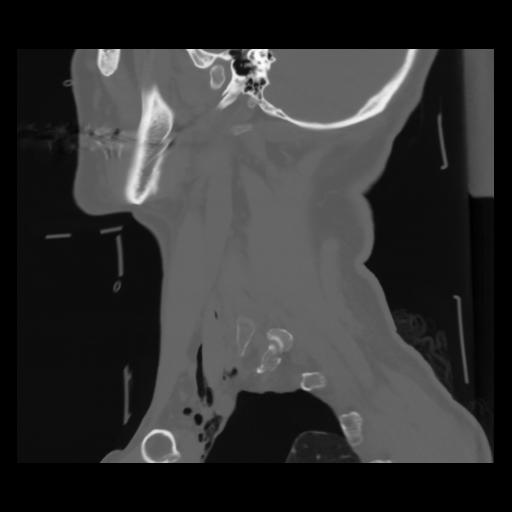

14 P.BLANDAS,,Sagittal,2.000,P.BLANDAS,Sagittal,